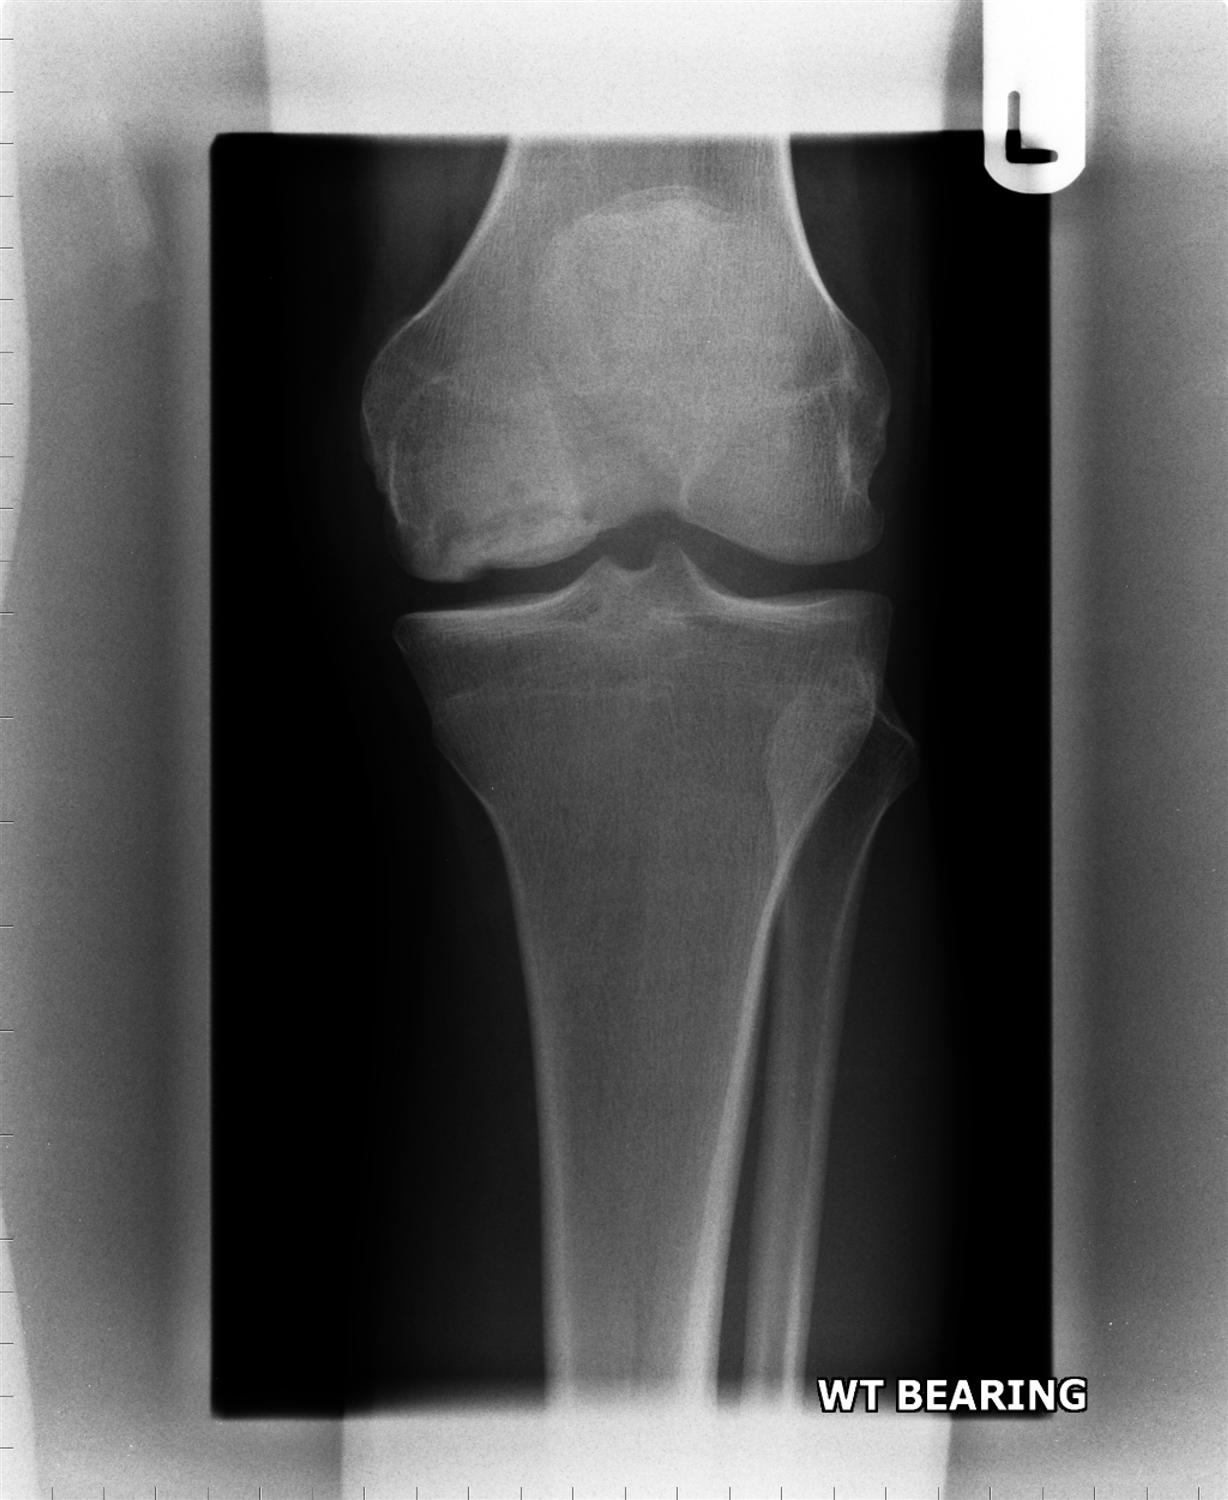

Locking Knee Osteochondritis Dissecans . The clinical manifestations and diagnosis of ocd and other causes of knee, elbow, or ankle pain in the young athlete are discussed. Osteochondritis dissecans of the knee is a relatively rare condition, categorized as a form of osteonecrosis that affects the. Diagnosis may be made radiographically. Osteochondritis dissecans happens when a section of bone in one of your joints loses its blood supply and becomes soft and weak. It mostly affects the femoral condyles, especially the medial condyle on the lateral joint surface (±80%). There are two main places in the knee joint where osteochondritis dissecans can appear. It occurs when a small segment of bone begins to crack and separate from its. Osteochondritis dissecans is a pathologic lesion affecting articular cartilage and subchondral bone with variable clinical patterns. Osteochondritis dissecans (ocd) is a condition that develops in joints, most often in children and adolescents. Osteochondritis dissecans is a disease that affects the bone and cartilage, most often in the knee in children and adolescents, causing pain,.

There are two main places in the knee joint where osteochondritis dissecans can appear. Osteochondritis dissecans happens when a section of bone in one of your joints loses its blood supply and becomes soft and weak. Osteochondritis dissecans of the knee is a relatively rare condition, categorized as a form of osteonecrosis that affects the. Diagnosis may be made radiographically. Osteochondritis dissecans (ocd) is a condition that develops in joints, most often in children and adolescents. Osteochondritis dissecans is a pathologic lesion affecting articular cartilage and subchondral bone with variable clinical patterns. It occurs when a small segment of bone begins to crack and separate from its. It mostly affects the femoral condyles, especially the medial condyle on the lateral joint surface (±80%). The clinical manifestations and diagnosis of ocd and other causes of knee, elbow, or ankle pain in the young athlete are discussed. Osteochondritis dissecans is a disease that affects the bone and cartilage, most often in the knee in children and adolescents, causing pain,.

Locking Knee Osteochondritis Dissecans There are two main places in the knee joint where osteochondritis dissecans can appear. Osteochondritis dissecans (ocd) is a condition that develops in joints, most often in children and adolescents. It occurs when a small segment of bone begins to crack and separate from its. It mostly affects the femoral condyles, especially the medial condyle on the lateral joint surface (±80%). Osteochondritis dissecans is a pathologic lesion affecting articular cartilage and subchondral bone with variable clinical patterns. There are two main places in the knee joint where osteochondritis dissecans can appear. Osteochondritis dissecans of the knee is a relatively rare condition, categorized as a form of osteonecrosis that affects the. The clinical manifestations and diagnosis of ocd and other causes of knee, elbow, or ankle pain in the young athlete are discussed. Osteochondritis dissecans is a disease that affects the bone and cartilage, most often in the knee in children and adolescents, causing pain,. Diagnosis may be made radiographically. Osteochondritis dissecans happens when a section of bone in one of your joints loses its blood supply and becomes soft and weak.